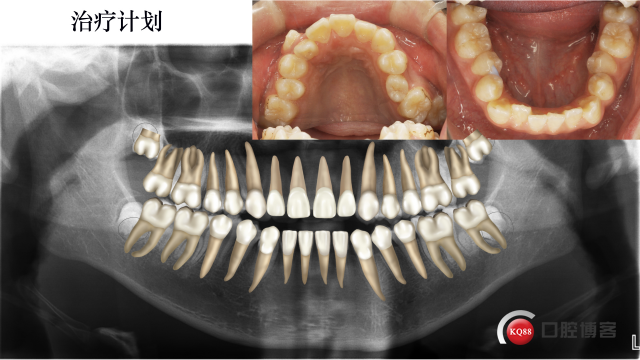

治疗计划:

拔除37,47,全口固定矫正,使用低转矩DamonQ金属自锁托槽,粘接全口托槽

42.41.31.32倒粘(托槽转矩从-11度变成+11度)、通过配合Damon含铜镍钛弓丝扩大上颌牙弓,在13和25处放置推簧,待推出足够空间在将13,25纳入牙弓。下颌排齐后在外斜线处植入2*10mmVector支抗钉整体远移下牙弓,调整磨牙尖牙关系及覆合覆盖问题。要求患者进行舌肌锻炼。

我们预期结果是这样